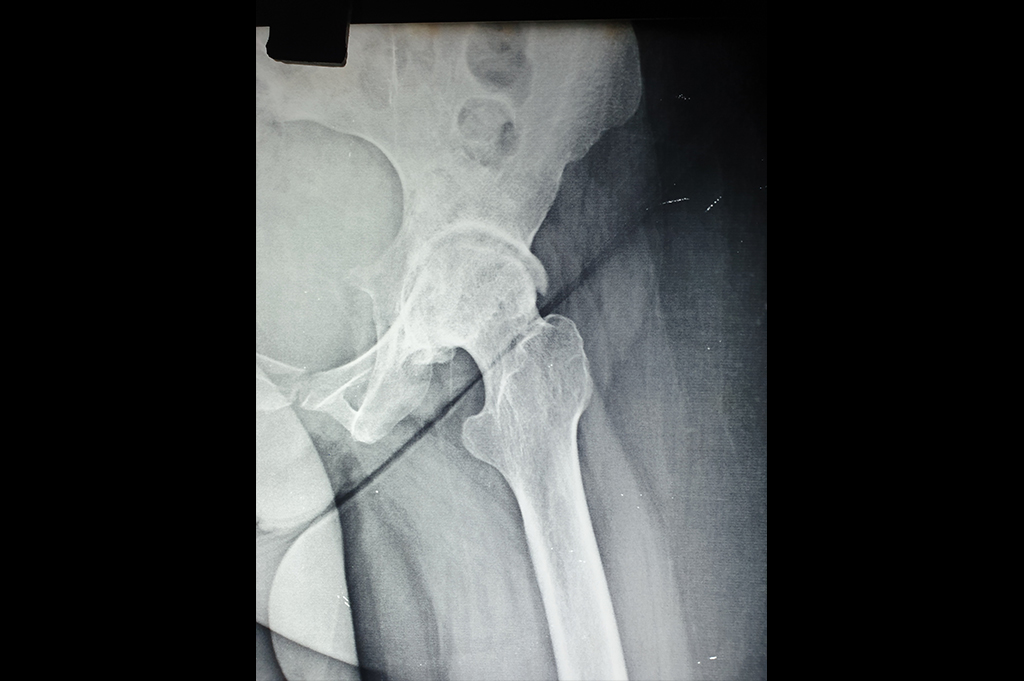

Intertrochanteric Fracture